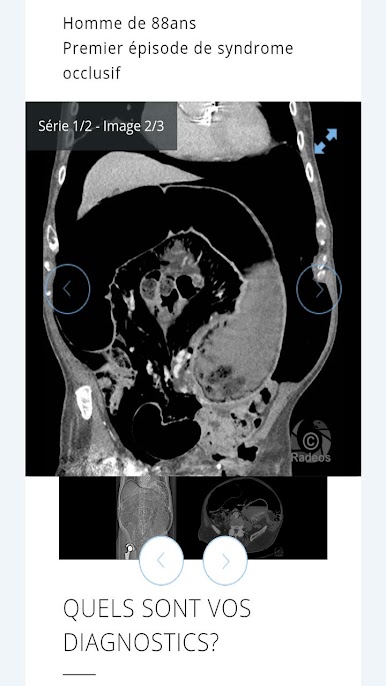

The largest French bank of clinical cases of medical imaging and radiology in your pocket!

You can test your knowledge with the radiological case of day and customized quiz.

Consultation with images of hundreds of typical and rare cases is simple, all accompanied by explanatory captions and course records. All imaging modalities are represented: CT, MRI, ultrasound, PET-CT scans, interventional radiology angiography.